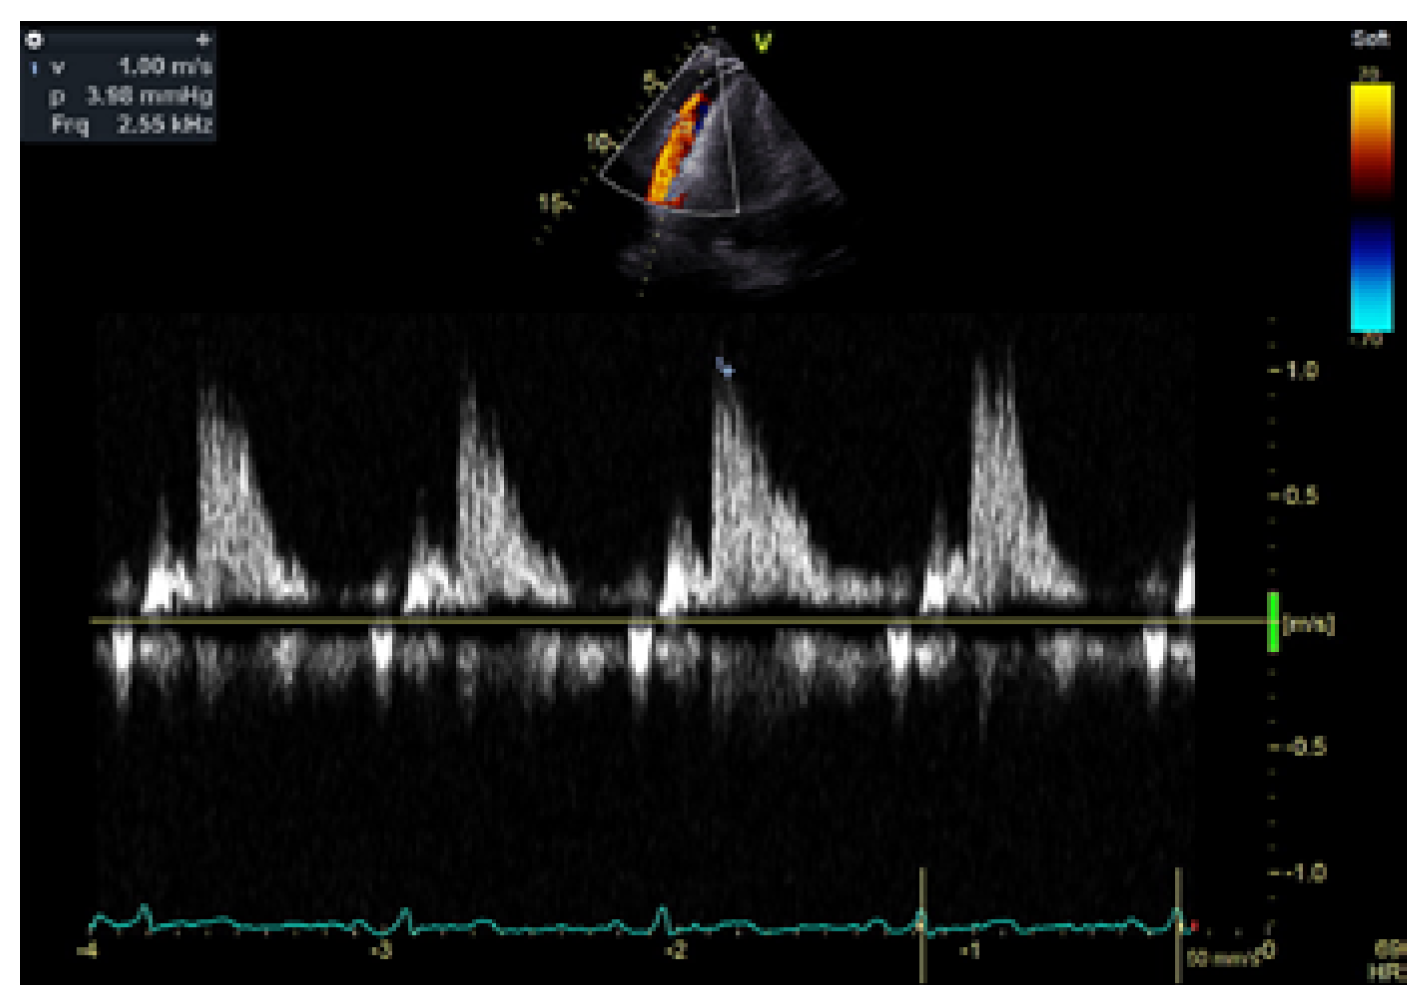

Intrapericardial Doppler Flow Signals in a Patient with Pericardial Effusion

Case Description